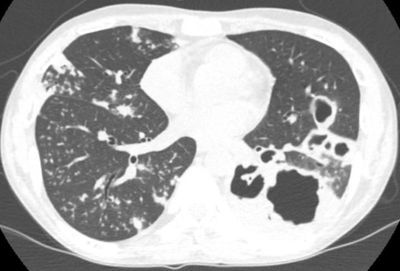

New research identifies how immune activation with checkpoint inhibitors can sometimes lead to rapidly progressive tuberculosis